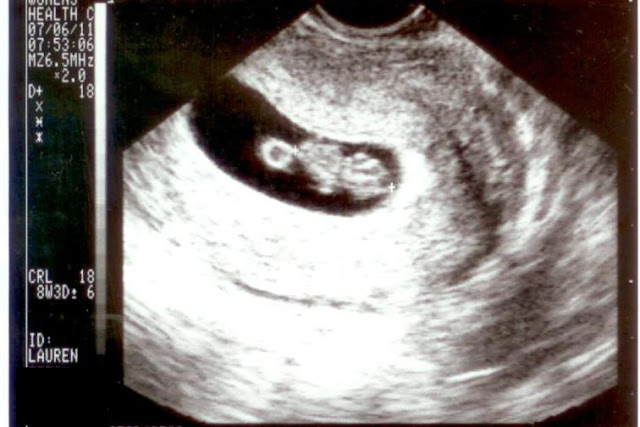

This isn't from today. This was taken at our 8 week checkup. The head is on the right in the picture, you can sort of see arm and leg buds, and the yolk sack is on the left hand side.

The pitiful little phone picture we used to share the news with those we weren't able to see when we told. (We told at 8 weeks this time - on July 8th.)